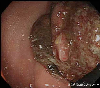

A case of rectal malignant melanoma with typical characteristic findings.

Endoscopy

Malignant melanoma/